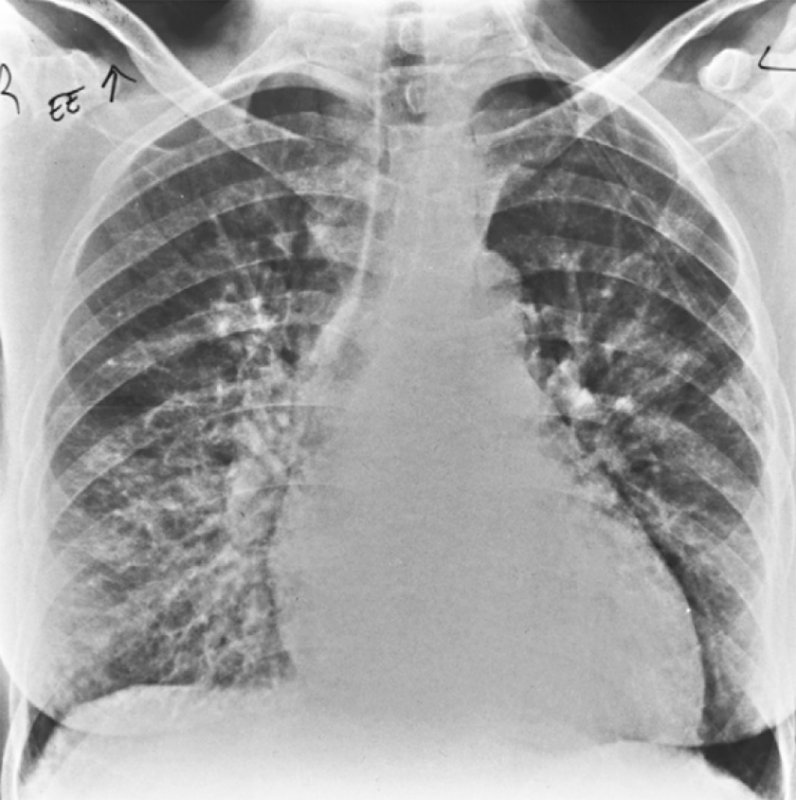

Синдром Гудпасчера – системный капиллярит, характеризующийся преимущественным поражением базальных мембран гломерулярного аппарата по типу гломерулонефрита (с гематурией) и альвеол легких по типу геморрагического пневмонита (с легочными кровотечениями). Рентгенологическая картина характеризуется появлением участков альвеолярной инфильтрации в легких. На рисунке 3 продемонстрированы интерстициальные изменения в легких, характерные для этой патологии.

Рисунок 3. Синдром Гудпасчера: Интерстициальные изменения в легких. Усиление интерстициального компонента легочного рисунка с обеих сторон, определяются ретикулярные и множественные мелкоочаговые тени. Изменения наиболее выражены в нижних и средних отделах легочных полей